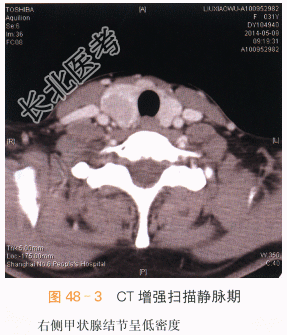

影像学资料如图48-1~图48-4所示。

本案例CT扫描见右侧甲状腺增大,结节与正常甲状腺分界不清,呈低密度,见沙砾样钙化(见图48-1),增强后呈低度强化,甲状腺包膜不完整,(见图48-2~图48-4),结合超声检查,考虑甲状腺癌。